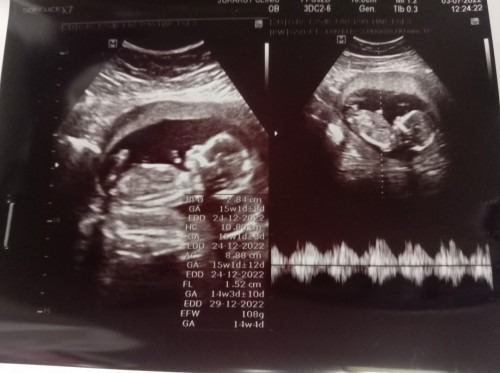

Post reply image